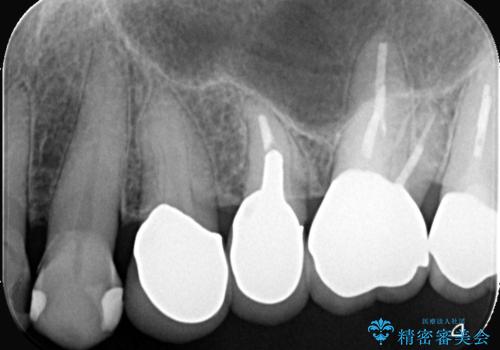

クラウンの不適により境目に汚れが溜まり、黒く見えていました。

古いクラウンを除去し、不適部位から中で広がっていたカリエスを除去したのちCRにて築造、仮歯を経てセラミッククラウンをセットしています。